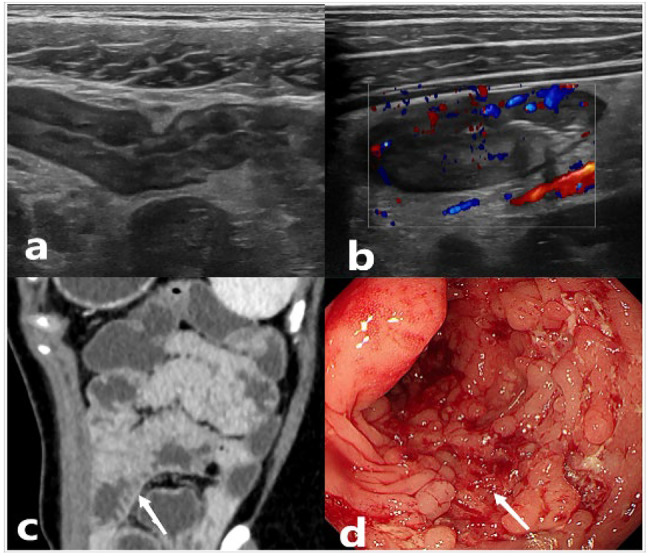

In addition, in group 1, the diagnostic potential of the IBUS-SAS was significantly superior to that of the SES-CD and MDCTEs (AUC 0.923, 0.801, 0.855, respectively), with IBUS-SAS had the highest diagnostic value for assessing disease activity. The Delong test revealed significant differences in diagnostic efficacy when comparing IBUS-SAS to SES-CD and IBUS-SAS to MDCTEs. In group 2, the diagnostic potential of the IBUS-SAS was significantly superior to that of the SES-CD and MDCTEs (AUC 0.925, 0.850, 0.909, respectively), with IBUS-SAS had the highest diagnostic value for assessing disease moderate-to-severe activity, but without a significant difference. In both groups of studies, the diagnostic potential of the SES-CD, which is often used as a standard, was inferior to that of IBUS-SAS or MDCTES. Due to the fact that CD is a transmural disease. Endoscopy is able to assess the degree of mucosal remission in the intestinal cavity, it cannot accurately evaluate the improvement of the entire intestinal wall. Conversely, IBUS-SAS, with its capacity to probe deeper intestinal layers, offers a distinct advantage in detecting submucosal and transmural inflammation. This capability is instrumental in elucidating the discrepancies observed in the diagnostic performance of SES-CD versus IBUS-SAS. The ultrasound’s penetration beyond the mucosal surface allows for a more comprehensive assessment of the disease’s impact on the intestinal wall, thereby providing a more accurate representation of the inflammatory burden. Furthermore, complications such as luminal fibrous stenosis in CD patients can impede endoscopic detection of lesions. The stenosis may obstruct the passage of the endoscope, precluding a thorough examination of the affected areas. IBUS-SAS will play an essential role in the continuous detection of CD disease activity in the future. In addition, similar to the previous report [28, 31–33], the IUS scores revealed a strong correlation with the CDAI. In this study, IBUS-SAS, SES-CD, and MDCTEs showed significant positive correlations with CDAI (r = 0.874, r = 0.677, and r = 0.762, respectively). This suggests that IBUS-SAS has a greater ability to predict treatment efficacy before a patient’s clinical symptoms resolve. Specifically, the high correlation between IBUS-SAS and CDAI scores indicates a close relationship between the ultrasound assessment of intestinal wall inflammation and the clinical manifestations of CD as measured by CDAI. This strong association implies that changes in IBUS-SAS scores may reflect changes in disease activity, thereby providing a sensitive indicator of the patient’s response to treatment. Figure 3 was a representative case of Crohn’s disease in which IUS, CTE, and endoscopic findings are well consistent with the clinical.

Fig. 3.

IUS, CTE, and endoscopic results in a representative Crohn’s disease patient. A 22-year-old male was diagnosed as A2L3B2 according to the Montreal classification. a: IUS shows thickening and loss of stratifcation of the terminal ileal wall; b: Color Doppler imaging reveals that the terminal ileum has full blood flow signals with a score of 3; c: CTE reveals multiple diffuse intestinal wall thickening with comb-like features; d: Colonoscopy finds extensive ileocecal mucosal ulceration and typical lithoid hyperplasia